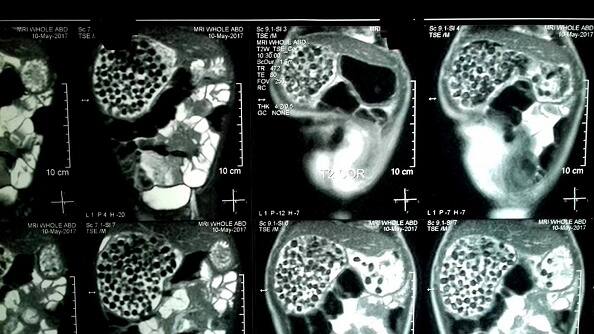

OMG! एक्स-रे में इस आदमी के पेट से दिखे पत्थर, सिक्के और बोतल के ढक्कन, जानें फिर क्या हुआ

इस ऑपरेशन के तहत जियांग की एंडोस्कॉपी और गैस्ट्रोकॉपी भी हुई.

जियांग ने बताया कि उसे जब भी एंजाइटी होती थी तो वो ये चीजें निगल लेता था. ऐसा करने से उसकी एंजाइटी शांत हो जाती थी.